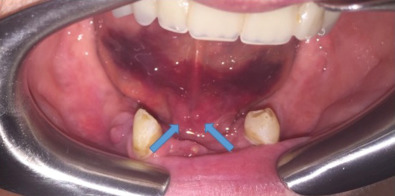

Intraoral hard tissue exam (bone): The hard tissue exam includes evaluation of the maxillary, mandibular, alveolar, and palatal bone, as well as the dentition. Fractures of the mandible or dentoalveolar segment often result in interdental step-offs, increased dental spacing, mobility of dentoalveolar segments (two or more teeth moving as a unit). More subtle findings may include crepitus, bleeding from the gingival sulcus, gingival lacerations or floor of mouth ecchymoses.

Intraoral hard tissue exam (dentition): The surgeon must first account for all preexisting teeth, teeth fragments or restorations. If there is avulsion or loss of a sizeable portion of a tooth, the fragment should be assumed to be in the oral cavity, airway, or GI tract until proven otherwise. Radiographs of the head, neck, chest, and abdomen (KUB) should be obtained to locate displaced teeth unable to be located to rule out aspiration. An understanding of the types of restorations (e.g. fixed/removable prostheses, implants, crowns, fillings, and orthodontic appliances) is useful in determining the extent of the injury and account for displacement. Be aware of indirect dental injury with forced occlusion of teeth from a superiorly directed force on the chin resulting in crown and/or root fractures of the posterior dentition.

Next, each remaining tooth and restoration should be evaluated systematically (see Classification section ). Transillumination of visible light along the long axis of the tooth can identify subtle dental injuries to enamel. Each tooth should be evaluated for mobility, both individually or along with its adjacent teeth (indicating a dentoalveolar fracture). Mobility of an individual tooth can indicate luxation of the entire tooth or a root fracture that can require dental radiographs to diagnose. The clinician should then evaluate the alignment of the dental arches. Teeth are most commonly displaced in a buccolingual direction due to the vector of trauma perpendicular to the tooth’s long axis. A tilting of the occlusal plane can indicate luxation or intrusion injuries, but may indicate maxillary or mandibular fracture. Each tooth should be tested for mobility in all dimensions with care not to avulse loose teeth or dentoalveolar segments. A commonly used mobility index is the Miller classification, in which tooth mobility is evaluated using two hard objects (e.g. two tongue depressors). If a tooth is nondisplaced but mobile, this may indicate either preexisting periodontal disease or a crown/root fracture. Dental fractures more coronally positioned generally have more mobility.